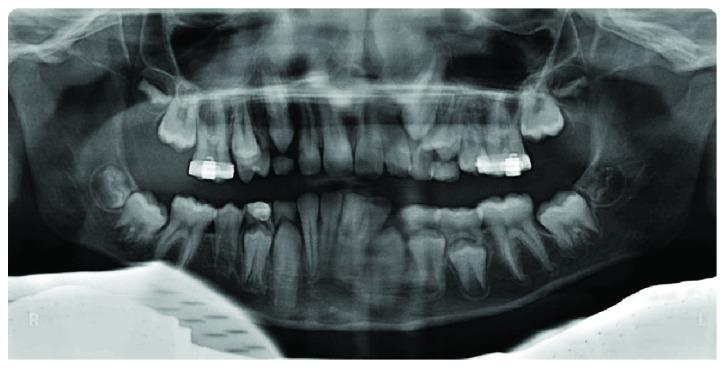

轻松实现间隙恢复:一例严重低位阻生乳磨牙病例

Space Regaining Made Easy: The Case of a Severely Infraoccluded Primary Molar.

Infraocclusion of deciduous molars is a quite common but challenging clinical situation that a paediatric dentist has to face in his everyday practice. This anomaly can lead to space loss, eruption disturbances of the permanent successor, and deformation of the occlusal plane. A case of a severely infraoccluded primary molar is presented. The treatment was carried out using a compressed NiTi wire applied only to the adjacent teeth. In three months, the space was recovered, and the infraoccluded temporary molar was extracted. After one year, the permanent successor erupted without any complication. The technique presented can be considered minimally invasive, and it involves cost- and time-efficient mechanics.

摘要

乳牙低位咬合是儿科牙医在日常临床实践中经常遇到但颇具挑战性的情况。这种异常可能导致间隙丧失、恒牙胚萌出障碍以及咬合平面变形。本文介绍了一例严重低位咬合的乳牙病例。治疗采用仅应用于相邻牙齿的压缩镍钛丝。三个月后,间隙恢复,低位咬合的乳牙被拔除。一年后,恒牙顺利萌出,未出现任何并发症。所介绍的技术可被视为微创技术,且具有成本效益高和省时的特点。